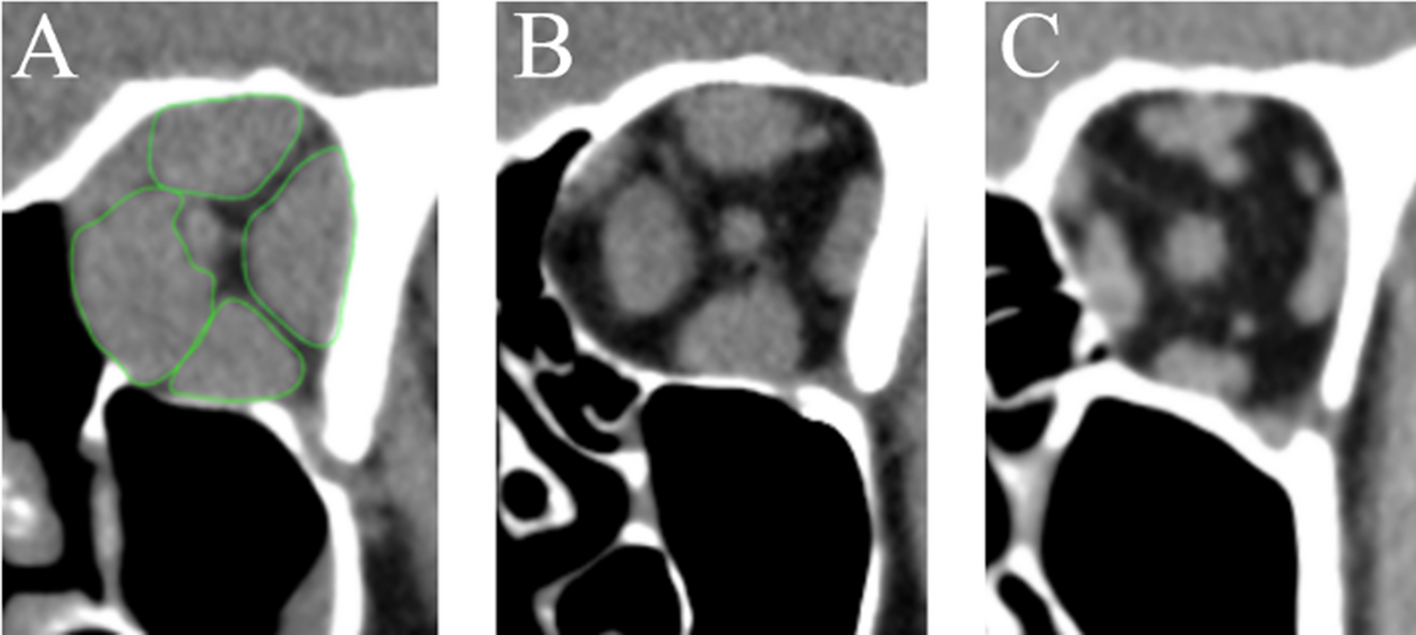

Figure 2

Coronal reconstructed CT images (orthogonal to the optic nerve) (A) patient with TED + DON and massive enlargement of the EOM (measured muscles exemplary outlined in green); (B) patient with TED only and substantial increase in muscle volume; (C) healthy control group orbit with normal muscle dimensions.